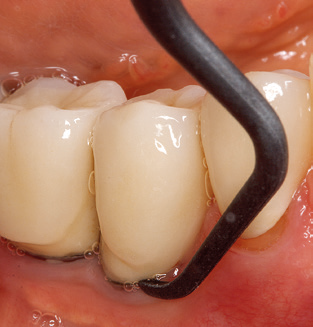

Fig. 4: Flexible probes with millimetre markings are recommended for the probing of dental implants (e.g. Colorvue Kit PCV11KIT6, Hu­Friedy). – Fig. 5a and b: A straight working tip (1P, W&H Dentalwerk Bürmoos GmbH) is a suitable instrument for use on all natural teeth. – Fig. 6: Curved working tips (3Pr/3Pl, W&H Dentalwerk Bürmoos GmbH) lend themselves to the processing of difficult-to-reach areas of the tooth and root surfaces (e.g. furcations). – Fig. 7: The tapered, hexagonal implant cleaning tip (1I, W&H Dentalwerk Bürmoos GmbH) permits atraumatic and efficient cleaning of the crown and abutment surfaces. – Fig. 8: Titanium and carbon curettes are suitable instruments for the manual cleaning of the implant surfaces.

Of course, working tips for the cleaning of implant surfaces are also indispensable for SPT in patients fitted with implants. The implant cleaning attachment on the system used here is characterised by its tapered, hexagonal design. This design allows light, atraumatic penetration of the peri-implant pocket and displays a good cleaning performance (Fig. 7).

Following machine cleaning of the tooth and implant surfaces, the surfaces of the natural teeth are cleaned manually using standard hand instruments. When performing manual cleaning, particular attention must be given to maintaining the correct angle of application, appropriate sharpness, good support and working with the curette from apical to coronal. Either titanium or carbon curettes should be used for post-cleaning of the implant structures (Fig. 8). In addition to the use of ultrasonic devices, power jet devices can also be used in conservative dentistry. However, it must be taken into consideration that these procedures are not suitable for removing hard deposits and thus they cannot replace the use of hand instruments and ultrasonic instruments completely. In all cases, cleaning is followed by mechanical polishing of the accessible tooth and implant surfaces with polishing cups and polishing compounds (Fig. 9).